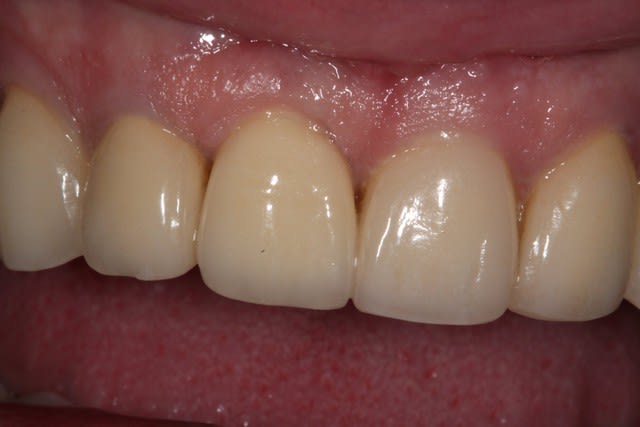

photo de controle vue vestibulaire et occlusale 8 mois post chir

puis à 2 ans post op

on constate que contrairement à la 11 surlaquelle il y a un affaissement de l'os vestibulaire

sur la 21 le volume est préservé

Si je peux me permettre, la 11 semble plus naturelle, car le zénith gingival est plus ovoide. La 21 possède certe plus de volume de tissu en vestibulaire, mais le collet gingivale est trop coronaire, effet de dent trapue.

L'ensemble est par contre sympa.